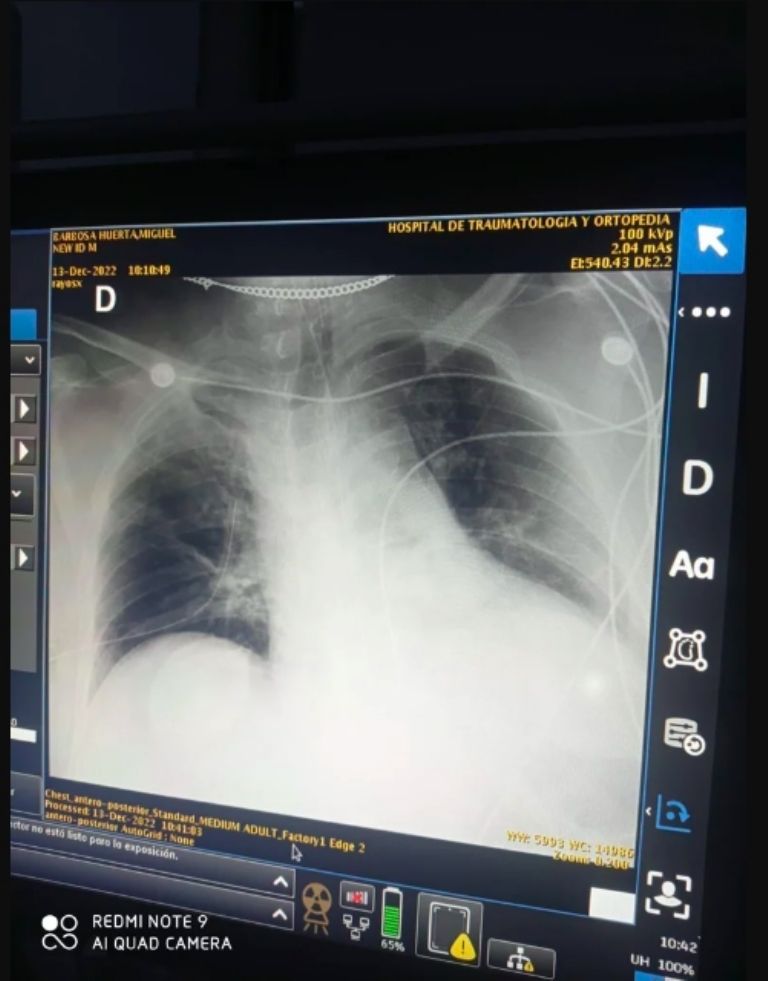

El ahora exgobernador de Puebla, padecía diabetes desde hace varios años, ya no contaba con una extremidad y debido a un contagio por Covid-19 tuvo diversos problemas de salud; por ello, el periodista Claudio Ochoa ha argumentado que en realidad se trató de una negligencia médica lo que lo llevó a perder la vida al interior de un nosocomio en la CDMX, incluso compartió una radiografía del exmandatario estatal que le daría la razón al punto que el comunicador expresa.

Ochoa quien se desempeña para el portal Latinus, manifestó que con apoyo de esa radiografía se pueden apreciar diversas irregularidades que dieron pie al desenlace que hoy es motivo de tres días de luto en la entidad. El antes mencionado aseguró que el militante de Movimiento Regeneración Nacional (Morena), no debió acudir a atenderse al Hospital de Traumatología y Ortopedia sin que debió ser llevado de urgencia al Hospital Civil ubicado en la capital poblana donde hay especialistas en temas cardiacos.

Al ser llevado a Traumatología y Ortopedia, Barbosa Huerta tuvo un mal procedimiento que derivó en la perforación de un pulmón, misma que se aprecia en la radiografía que éste obtuvo, afección que llevó a que se tomara la decisión de llevarlo de urgencia a la CDMX donde ya no se pudo hacer nada para estabilizarlo. Hasta ahora, esta teoría expuesta por el periodista de Latinus, no se ha confirmado o desechado por la familia del exgobernador ya que todo se ha centrado en los funerales de cuerpo presente que se llevan a cabo en la entidad que gobernó.